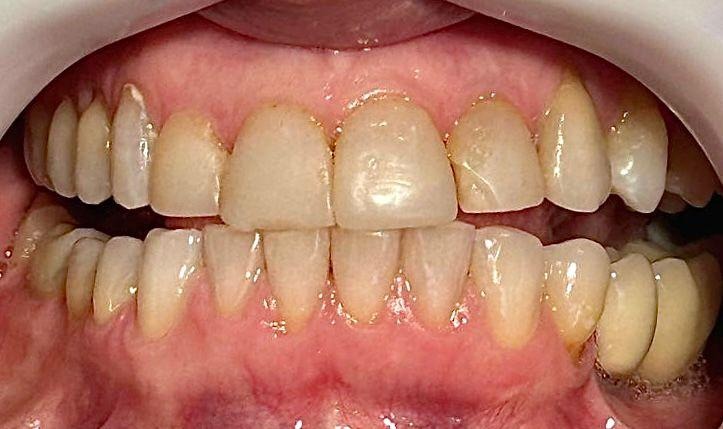

A coleta de dados foi iniciada com a realização de uma consulta inicial, na qual foi conduzida uma anamnese detalhada para levantamento do histórico médico e odontológico do paciente, bem como de suas principais queixas e expectativas em relação ao tratamento estético proposto. Em seguida, foi realizado um exame clínico minucioso com o objetivo de avaliar as facetas previamente instaladas, observando critérios como adaptação marginal, integridade do material restaurador e condições periodontais adjacentes. A saúde bucal geral do paciente também foi analisada nesta etapa, no aspecto inicial foi observado o acúmulo de biofilme causado pela má adaptação cervical, retração gengival, trincas e fraturas derivadas da oclusão desbalanceada, conforme apresenta a figura 1,2,3 e 4.

Figura 2: Vista frontal, região anterior